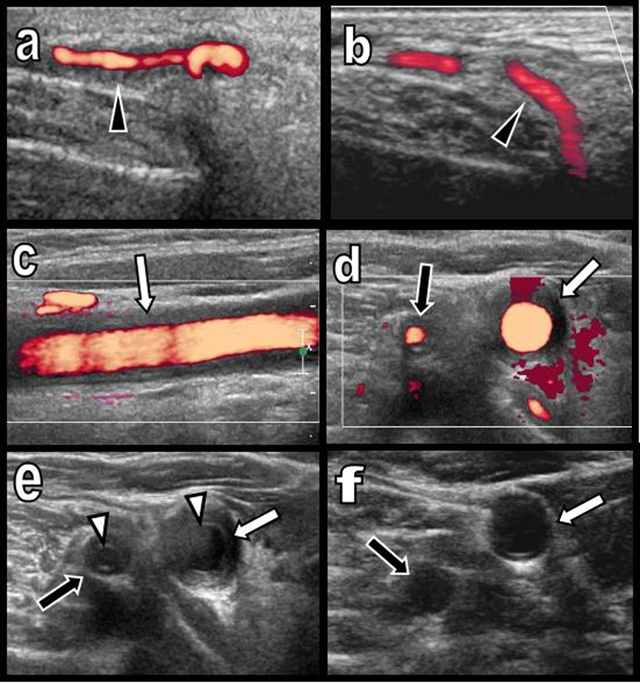

A 65-year-old woman presented with a three-month history of persistent ocular-nasal catarrh, sub-febrile state, myalgia, night sweats, weight loss and early daily bi-temporal pain. Severe biological inflammatory syndrome with CRP at 105 mg/l and sedimentation rate at 97 mm was present. Colour Doppler Ultrasound (CDU) (Figure 1) showed a typical inflammatory “halo sign” (black arrowhead on a) of the temporal arteries. A similar “halo sign” was found along the common carotid (white arrows on c, d, and e) and vertebral arteries (black arrows on d and e). The intima remained visible (white arrowheads on e). Computed Tomography (CT) angiography (Figure 2) showed blur homogeneously enhancing wall thickening of the aortic arch (white arrows on a and d) and of its large emerging arteries (white arrows on b). The axillary arteries were also affected (black arrows on a). Moderate thickening of the abdominal visceral aorta was also found (not illustrated). Hypodensity of the intima contrasted with enhancement of the inflamed media (white arrowheads on b). Temporal artery biopsy (Figure 3a and b) confirmed typical giant cell arteritis (GCA) with involvement of the media (yellow star) and adventice (white star) by chronic lymphocytic inflammation. Reactive intimal hyperplasia (black star) causing luminal collapse (white arrow), characteristic fragmentation of the internal elastic lamina (black arrows) and giant cells (black circles) were also diagnosed. Classical massive corticosteroid treatment was immediately started with rapid clinical and biological improvement. The “halo sign” and diffuse arterial thickening had, drastically, nearly completely resolved on post-therapeutic CDU (Figure 1b and f) and CT (Figure 2c and e) nine months later.

Figure 1

Colour Doppler Ultrasound of the temporal artery before (a) and after treatment (b) and of the right primitive carotid and vertebral arteries before (c, d, e) and after treatment (f).